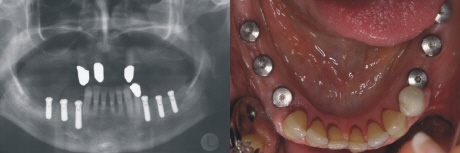

Implantation

Zum Ersatz der fehlenden Zähne wurden auf jeder Seite drei Implantate eingebracht. Auf dem rechten Bild sieht man die Verschlusskappen der sechs eingebrachten Implantate.